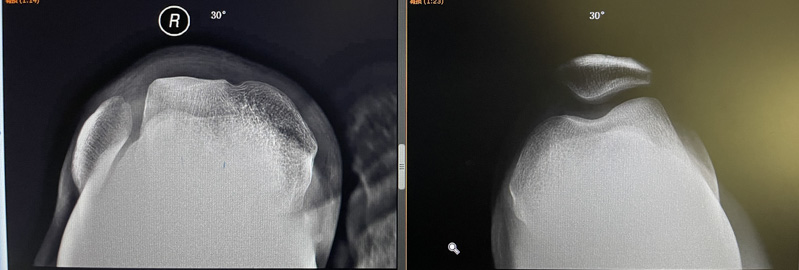

▲跟健側對比:膝關節屈膝30°,髕骨脫位

經仔細檢查后,柳州市人民醫院運動醫學科副主任韋釗嵐發現王先生的膝關節屈曲30°時,髕骨就脫位跑到了股骨滑車外側,整個屈膝過程髕骨都不能復位,直到再次伸直膝關節,髕骨才能回位,這是很明顯的“屈曲型習慣性髕骨脫位”。